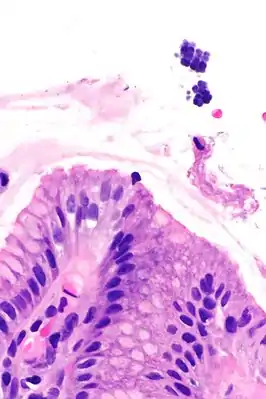

Сарцины (лат. Sarcina) — род грамположительных кокков, делящихся в трех взаимно перпендикулярных направлениях, образуя при этом кубические «тюки», от чего и получили своё название[1][2][3]. Сапрофиты, обычно неспороносны, неподвижны и непатогенны[1][4]. Способны к синтезу бактериальной целлюлозы[5]. Встречаются в почве, воде, воздухе и живых организмах[1]. Многие представители этого рода являются частью микрофлоры человека и обитают на коже[6] и в толстом кишечнике[7].

Типового представителя этого рода, Sarcina ventriculi, можно обнаружить на поверхности семян злаковых, в почве, кишечнике человека, кроликов и морских свинок[8].